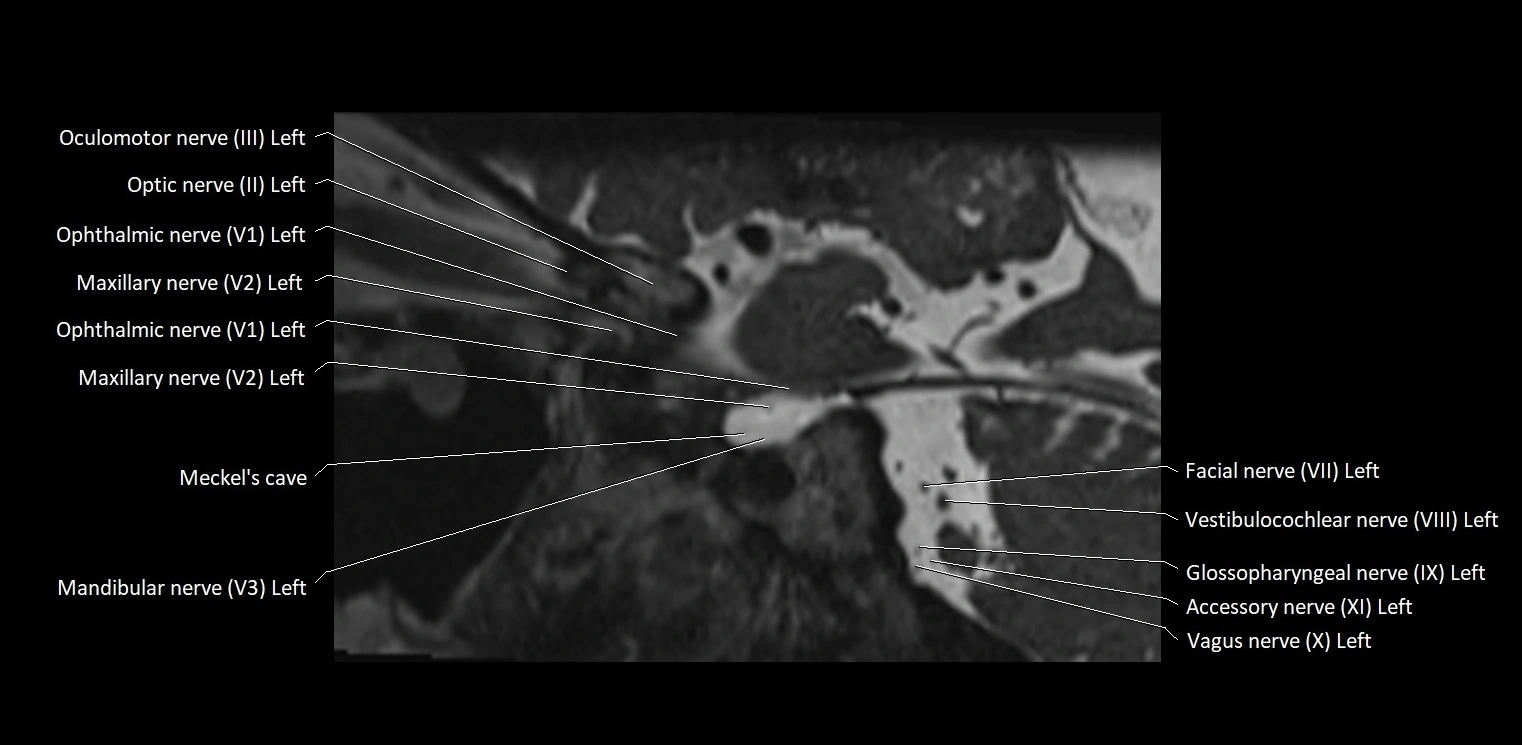

• The abducens nerve is a small, thin, linear structure

• Best visualized on high-resolution T2-weighted 3D MRI sequences (e.g., FIESTA or CISS)

• Seen as a hypointense (dark) line running from the brainstem at the pontomedullary junction, traversing the prepontine cistern, and entering Dorello’s canal under the petrosphenoidal ligament, then into the cavernous sinus, and finally the orbit

• May be challenging to visualize in standard MRI due to its small size

• Pathology may be inferred by absence, displacement, or enhancement of the nerve